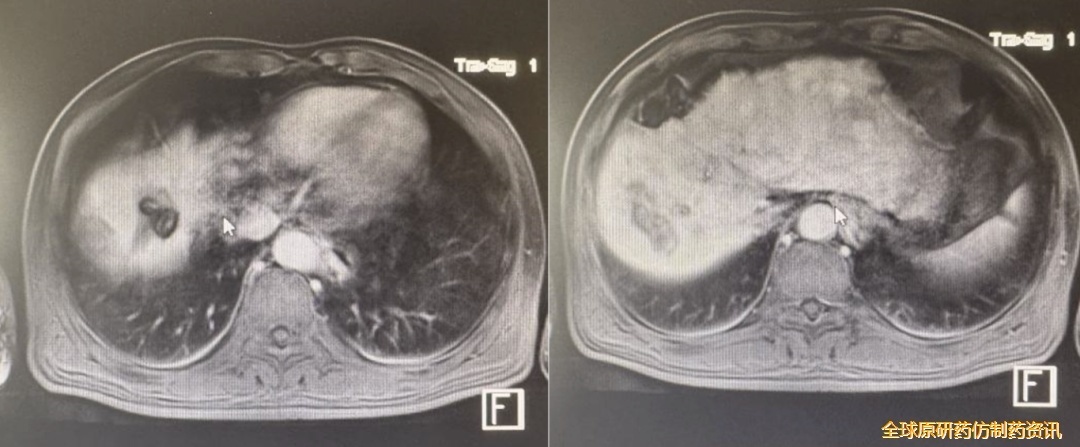

肝脏MRI(2024.3.24):肝癌术后复查,对比MRI老片示:肝右叶上段异常信号,考虑肝Ca,较前新发;肝胆特异期肝实质多发高信号结节,部分较前稍增大,考虑多腺泡硬化结节可能,建议随诊复查及结合肿瘤标志物检查。

图4 2024.3.24影像学复查